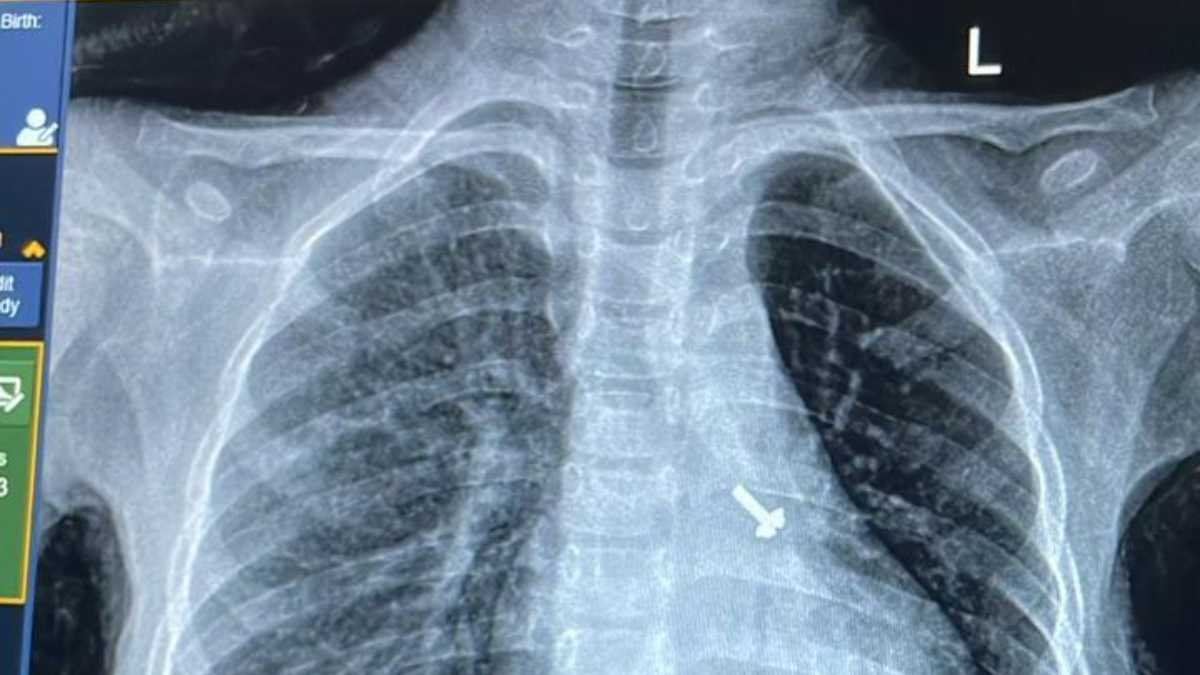

07 वर्ष के बच्चे के फेफड़े में फंसे पेंच को निकालकर एम्स के चिकित्सकों ने दिया जीवनदान

ऋषिकेश: अखिल भारतीय आयुर्विज्ञान संस्थान, ऋषिकेश के पल्मोनरी मेडिसिन विभाग की ओर से संचालित ब्रोंकोस्कोपी प्रयोगशाला में एक 07 वर्ष…